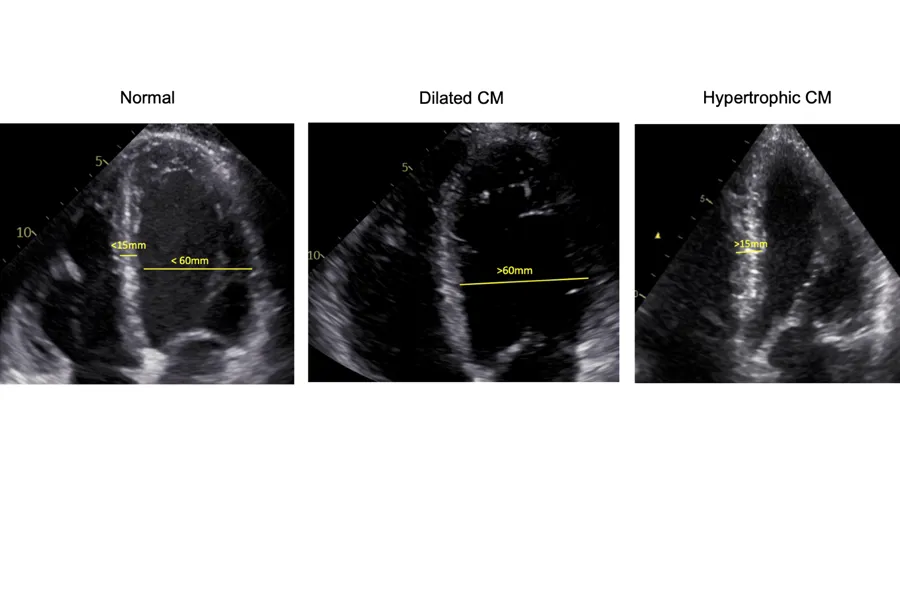

The research focuses on applying deep learning techniques to cardiac ultrasound imaging. We are investigating the capabilities of foundation models and self-supervised learning to automate measurements from echocardiograms, assess image quality, and improve diagnostic support. This work will help extend these models to new use cases in cardiac ultrasound, including the detection, characterization and progression study of cardiomyopathy.

The objective is to develop and validate deep learning models for diagnosing cardiomyopathy using cardiac ultrasound imaging, with a focus on hypertrophic and dilated cardiomyopathy. By leveraging self-supervised learning and foundation models, we aim to enhance diagnostic accuracy, automate measurements, and explore image-based assessments for tracking disease progression.